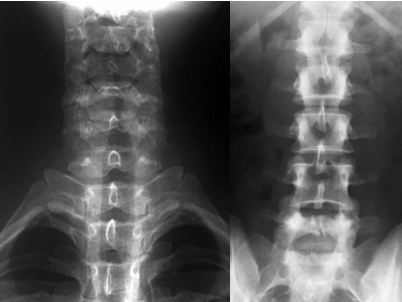

Lesiones En La Espalda Por Caidas Neurocirugia De La Torre